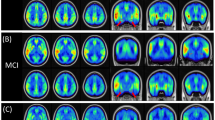

Figure 1 shows sections of T1-weighted anatomical images averaged over all HC with areas of lower CBFcorr in patients as revealed by the ANOVA analysis overlaid in yellow (P < 0.001 uncorrected) and red (P < 0.05, FWE corrected). Table 2 summarizes anatomic regions, cluster sizes, z values and MNI coordinates of peak locations. Lower CBFcorr in patients with MCI as compared to HC was found in the right and left superior parietal gyrus, the right and left angular gyrus, the left inferior parietal gyrus, the left and right middle temporal gyrus and the middle occipital gyrus. Only the differences in the right angular gyrus and in the left superior parietal lobe survived FWE correction for multiple comparisons. Patients with AD showed lower CBFcorr than HC in the right angular gyrus, in the left and right superior parietal gyrus, in the left and right inferior parietal lobe, in the right middle occipital gyrus, in left precuneus and caudate. The differences in CBFcorr attained statistical significance on an FWE-corrected level in the left superior parietal lobe, in the right angular gyrus, in the middle occipital lobe and in the left precuneus. There was only a small cluster in the middle cingulate where patients with MCI exhibited higher perfusion than patients with AD. No regions of hyperfusion were detected in patients with AD and MCI compared with HC according to the ANOVA analysis.